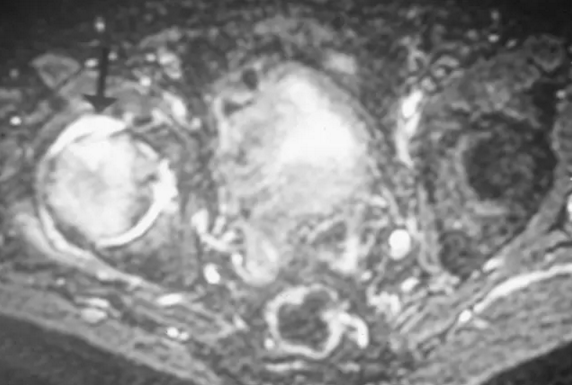

股骨头缺血坏死

T2压脂像在股骨头和颈部(箭头)内显示增强的信号,代表水肿。 STIR和脂肪饱和成像非常敏感。

T2压脂像显示了关节积液(箭头)和表示股骨头内的水肿的广泛的异常增加的信号。 存在股骨头的前部中的骨折。